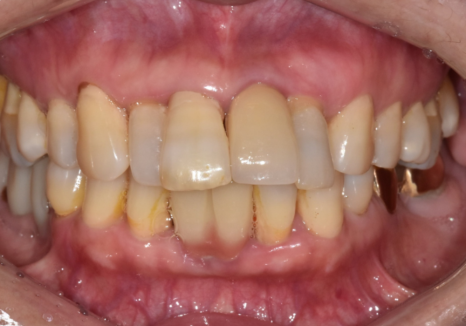

이 환자분은 “앞니가 흔들린다"는

불편감으로 오셨습니다.

확인해 보니 왼쪽 앞니는

오래전에 이미 임플란트를 해두신 상태였고,

임플란트 양옆의 치아가

흔들리는 상황이었습니다.

문제는 기존 임플란트 보철이

예전 치아 배열 기준으로

제작돼 있었다는 점이었는데요,

그 보철을 기준으로 새 보철을 맞추면

최종 결과가 다시

앞니가 튀어나와 보이는 형태로

갈 가능성이 있었습니다.

230826

그래서 기존 임플란트는

고정체(뿌리)는 그대로 두고,

보철만 제거한 뒤,

앞니 라인을

덜 도드라져 보이도록

다시 설계했습니다.

230826(전) 240619(후)

최종 보철은 형태와

색이 자연스럽게 정리됐고,

앞니가 도드라져 보이던 느낌도

부드럽게 잡혔습니다.